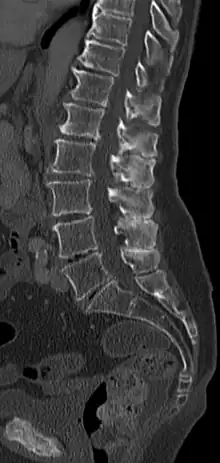

Colonne vertébrale en biseau (maladie de Baastrup) en coupe scanner sagittale. Les apophyses épineuses des vertèbres lombaires frottent les unes contre les autres et présentent des changements dégénératifs en conséquence.

La maladie de Baastrup est une pathologie caractérisée par une friction entre les apophyses épineuses des vertèbres lombaires. En réponse au stress subi, le tissu osseux s'élargit à l'extrémité de l'apophyse et accroît en fait la pathologie.